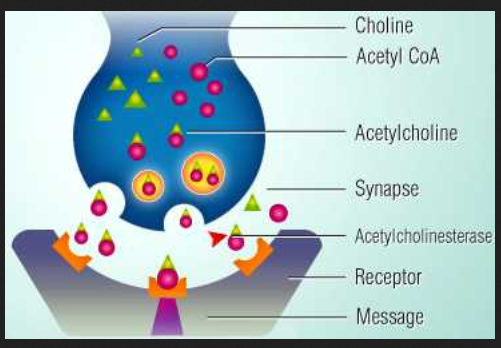

55 brain levels of thought

56 Basement levels of the 1993 bombing